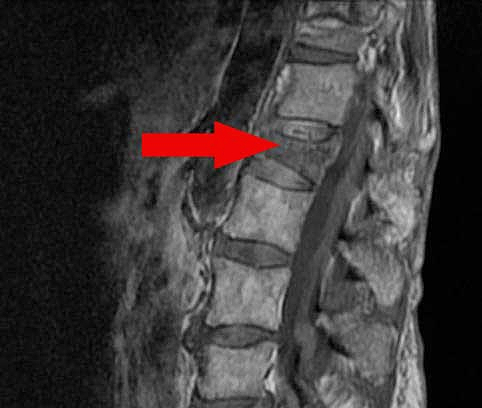

위 사진에서처럼 골절의 정도가 심하여 척추의 불안정성이 커진 경우는 반드시 수술이 필요합니다. 또는 골다공증으로 인해 추가적인 붕괴가 우려된다면 역시 적극적인 치료가 필요합니다. 일반적으로 압박된 부위에 골시멘트를 주입하는 척추 성형술을 시행하여 척추의 안정화를 목적으로 합니다.